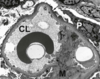

A 50 yo caucasian male presents with proteinuria >3g/day

on biopsy you see the attached image.

What is the antibody associated with this type of lesion?

where is the lesion located?

what should your work up include?

what is your prognosis?

Nephrotic Syndrome: Membranous glomerulonephrpathy

antibodies against the Phopholipase A2 receptor

immune complex deposition in situ on the subepithelial aspect of the BM

work up should include tests for SLE, RA and hepatitis serologies (looking for auto antibodies?) and

**age appropriate cancer screenings**

prognosis: “rule of thirds” 1/3 remission, 1/3 persistent proteinuria with stable renal function, 1/3 progress to ESRD